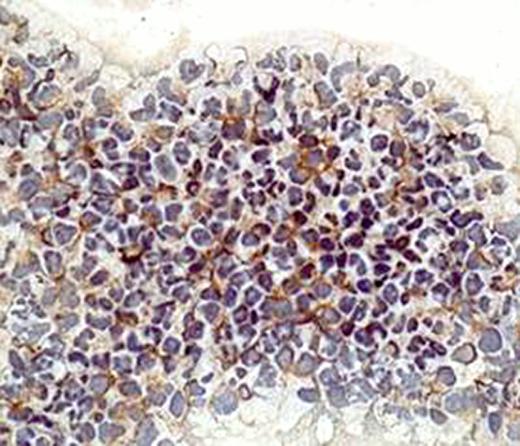

CD34+ cells from 98 newly diagnosed patients with MDS and 5 normal donor bone marrow specimens were sorted with CD34 isolation kit from Miltenyi Biotec. Total cellular RNA was isolated using Trizol, cDNA was obtained by using TaqMan reverse transcription reagent (Applied Biosystems). For real-time PCR, FAK assay were purchased from Applied Biosystems and analyzed with an Applied Biosystems Prism 7500 Sequencing detection system. GAPDH was used as internal control. Immunohistochemistry was used to detect FAK protein level in cytospin from MDS CD34+ cells. FAK antibody was obtained from abcam. FAK inhibitor was purchased from Santa Cruz Biotechnology.

For the 98 MDS patients studied, 78% were older than 60 years; by IPSS score, 17 (17.3%) low risk, 35 (35.7%) INT-1, 24 (24.5%) INT-2, 10 (10.2%) high risk, 12 (12.2%) not available. By cytogenetics, diploid 44 (45%), 20q- 7 (7%), -5/5q- 7 (7%), -7/7q- 7 (7%), -5/5q- and -7/7q- 6 (6%), 8+ 6 (6%), IM 6 (6%), MISC 14 (14%). By real-time PCR, we observed FAK overexpression in 28% of MDS CD34+ cells (fold 2.2–26). We then analyzed FAK protein expression in 10 MDS CD34+ cell cytospin with either higher or lower RNA expression by QPCR using immunohistochemistry. The protein expression patterns were 100% consistent with RNA expression level. This result suggests that FAK expression is upregulated in MDS CD34+ cells. We then performed analysis of clinical associations between FAK expression and clinical characteristics. No association was observed in particular between FAK expression and survival. Because of the potential role of FAK as a therapeutic target, we then studied the effects of FAK inhibition in cell lines. We studied FAK expression level in leukemia cell lines of AML origin and found high protein expression level of FAK in AML leukemia cell line OCI-AML3 and KG1. We treated these cells with FAK inhibitor 14 and detected a dose dependent anti-proliferative effect on both cell lines. Using Annexin V - FITC analysis by flow cytometry, we found the FAK inhibition could induce apoptosis in both cell lines at concentrations of 10uM both at 24 hours and 48 hours.